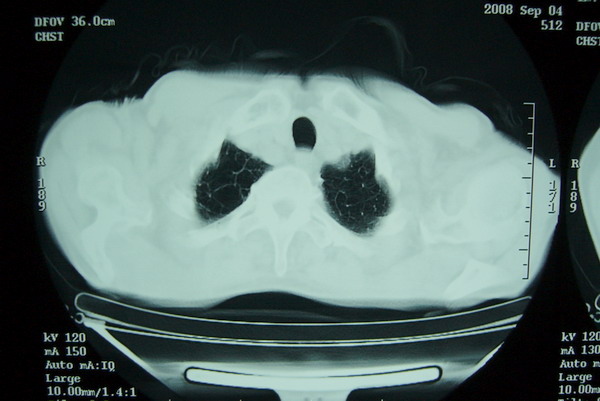

标题: CT15579:男 86岁 咳嗽 咳少量白痰 发热2天 吸烟史60年 [打印本页]

标题: CT15579:男 86岁 咳嗽 咳少量白痰 发热2天 吸烟史60年

右上周围型肺癌,慢支,肺气肿。

分叶及少量边缘性钙化,老年人,周围性肺癌首先考虑。

右肺上叶巨大软组织肿块,轮廓不规则,纵隔内有肿大淋巴结,首先考虑肺癌。

右上肺一不规则团块,边缘有分叶和毛刺,纵隔有淋巴结肿大。右肺周围性肺癌首先考虑。